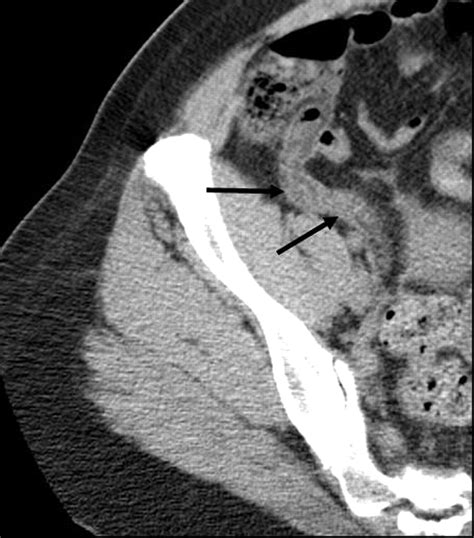

Medical professionals diagnose appendicitis through a combination of physical examinations, blood tests (to look for signs of infection), and imaging studies like ultrasound or CT scans. Relying on these medical tools is the only way to accurately determine if the appendix is in immediate danger of bursting.